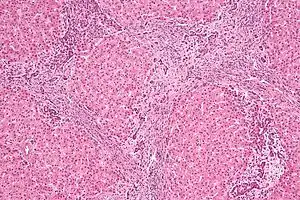

| Micrograph of focal nodular hyperplasia. H&E stain. | |

Focal nodular hyperplasia's most recognizable gross feature is a central stellate scar seen in 60–70% of cases. Microscopically, a lobular proliferation of bland-appearing hepatocytes with a bile ductular proliferation and malformed vessels within the fibrous scar is the most common pattern. Other patterns include telangiectatic, hyperplastic-adenomatous, and lesions with focal large-cell dysplasia.[2] Rarely, these lesions may be multiple or can occur as part of a syndrome with hemangiomas, epithelioid hemangioendothelioma, hepatic adenomas, fibrolamellar hepatocellular carcinoma, vascular malformations of the brain, meningiomas, and/or astrocytomas.[2]